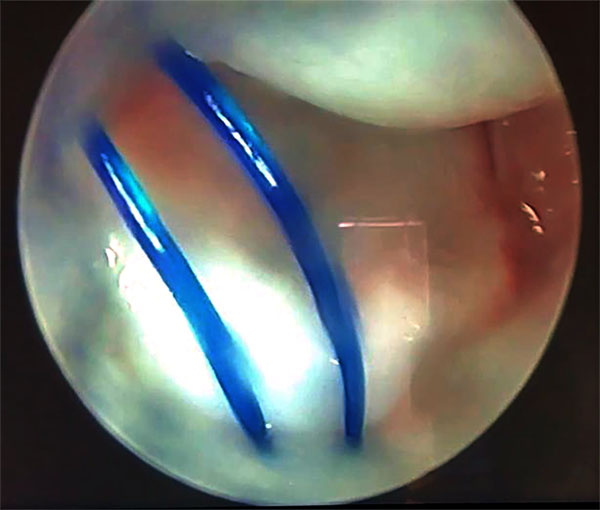

Luego realizamos una incisión de 5 mm entre los cabos de las suturas proximales, divulsionamos hasta cápsula y con visión 6r, realizamos un nudo simple de ambos extremos del hilo consiguiendo así la plicatura de la capsula dorsal (figs. 11 y 12).

Figuras 11 y 12: Muestran los hilos por portal radiocarpiano antes del anudado capsular y luego del anudado con la plicatura capsular.